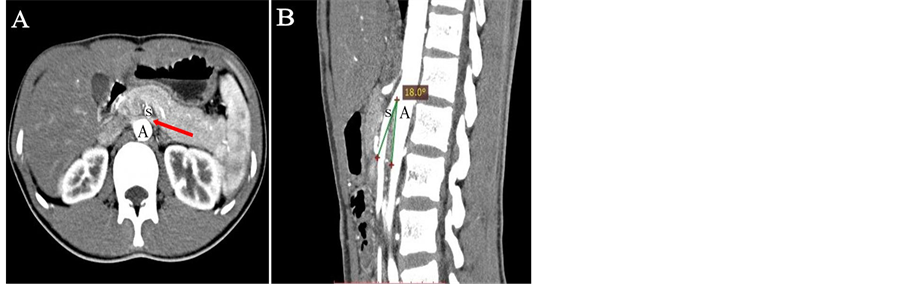

After admission, the patient had undergone cardiovascular examination including a chest X-ray and echocardiography that were normal. As there was no other signs indicative of secondary hypertension, a renal ultrasound with a Doppler renal arteries scan and a computed tomography angiography (CTA) were performed. Supine admission measurement in renal ultrasound examination showed an obvious stenosis and dilatation of the LRV without any signs of varices. The LRV was compressed in the angle between SMA and abdominal aorta, in which the proximal venous dilation was noted (antero-posterior diameter 0.92 cm in the hilar portion, 0.17 cm in the narrow portion, ratio 5.4. see Figure 1(a)). Doppler flow peak velocity was 252 cm/s in the narrow portion. CTA had revealed signs of LRV stenosis and dilation (see Figure 2), angle between aorta and SMA was about 18˚. The renal ultrasound and CTA results indicated this manifestation as NCP. Compared to invasive procedure left renal retrograde venography, non invasiveexaminations such as Doppler ultrasonography and CTA remain the main procedures to final diagnosis of NCP [4] [5] [6] . Our patient was conservatively observed without any anti-hypertensive drugs and be asked for putting on weight appropriately. He was followed up 3 months later and renal ultrasound revealed that the LRV compression was relieved (hilar portion 1.10 cm, narrow portion 0.20 cm, ratio 5.5; narrow portion flow peak velocity was 114 cm/s. see Figure 1(b)).

Figure 2. CTA shows the relationship of SMA (S), aorta (A) and LRV (arrow) in coronal (A) and sagittal (B) planes in this patient. (A) LRV is compressed when it crosses between aorta and SMA. (B) SMA compresses LRV with initial steep caudal descent with aorta at the angle of 18˚.